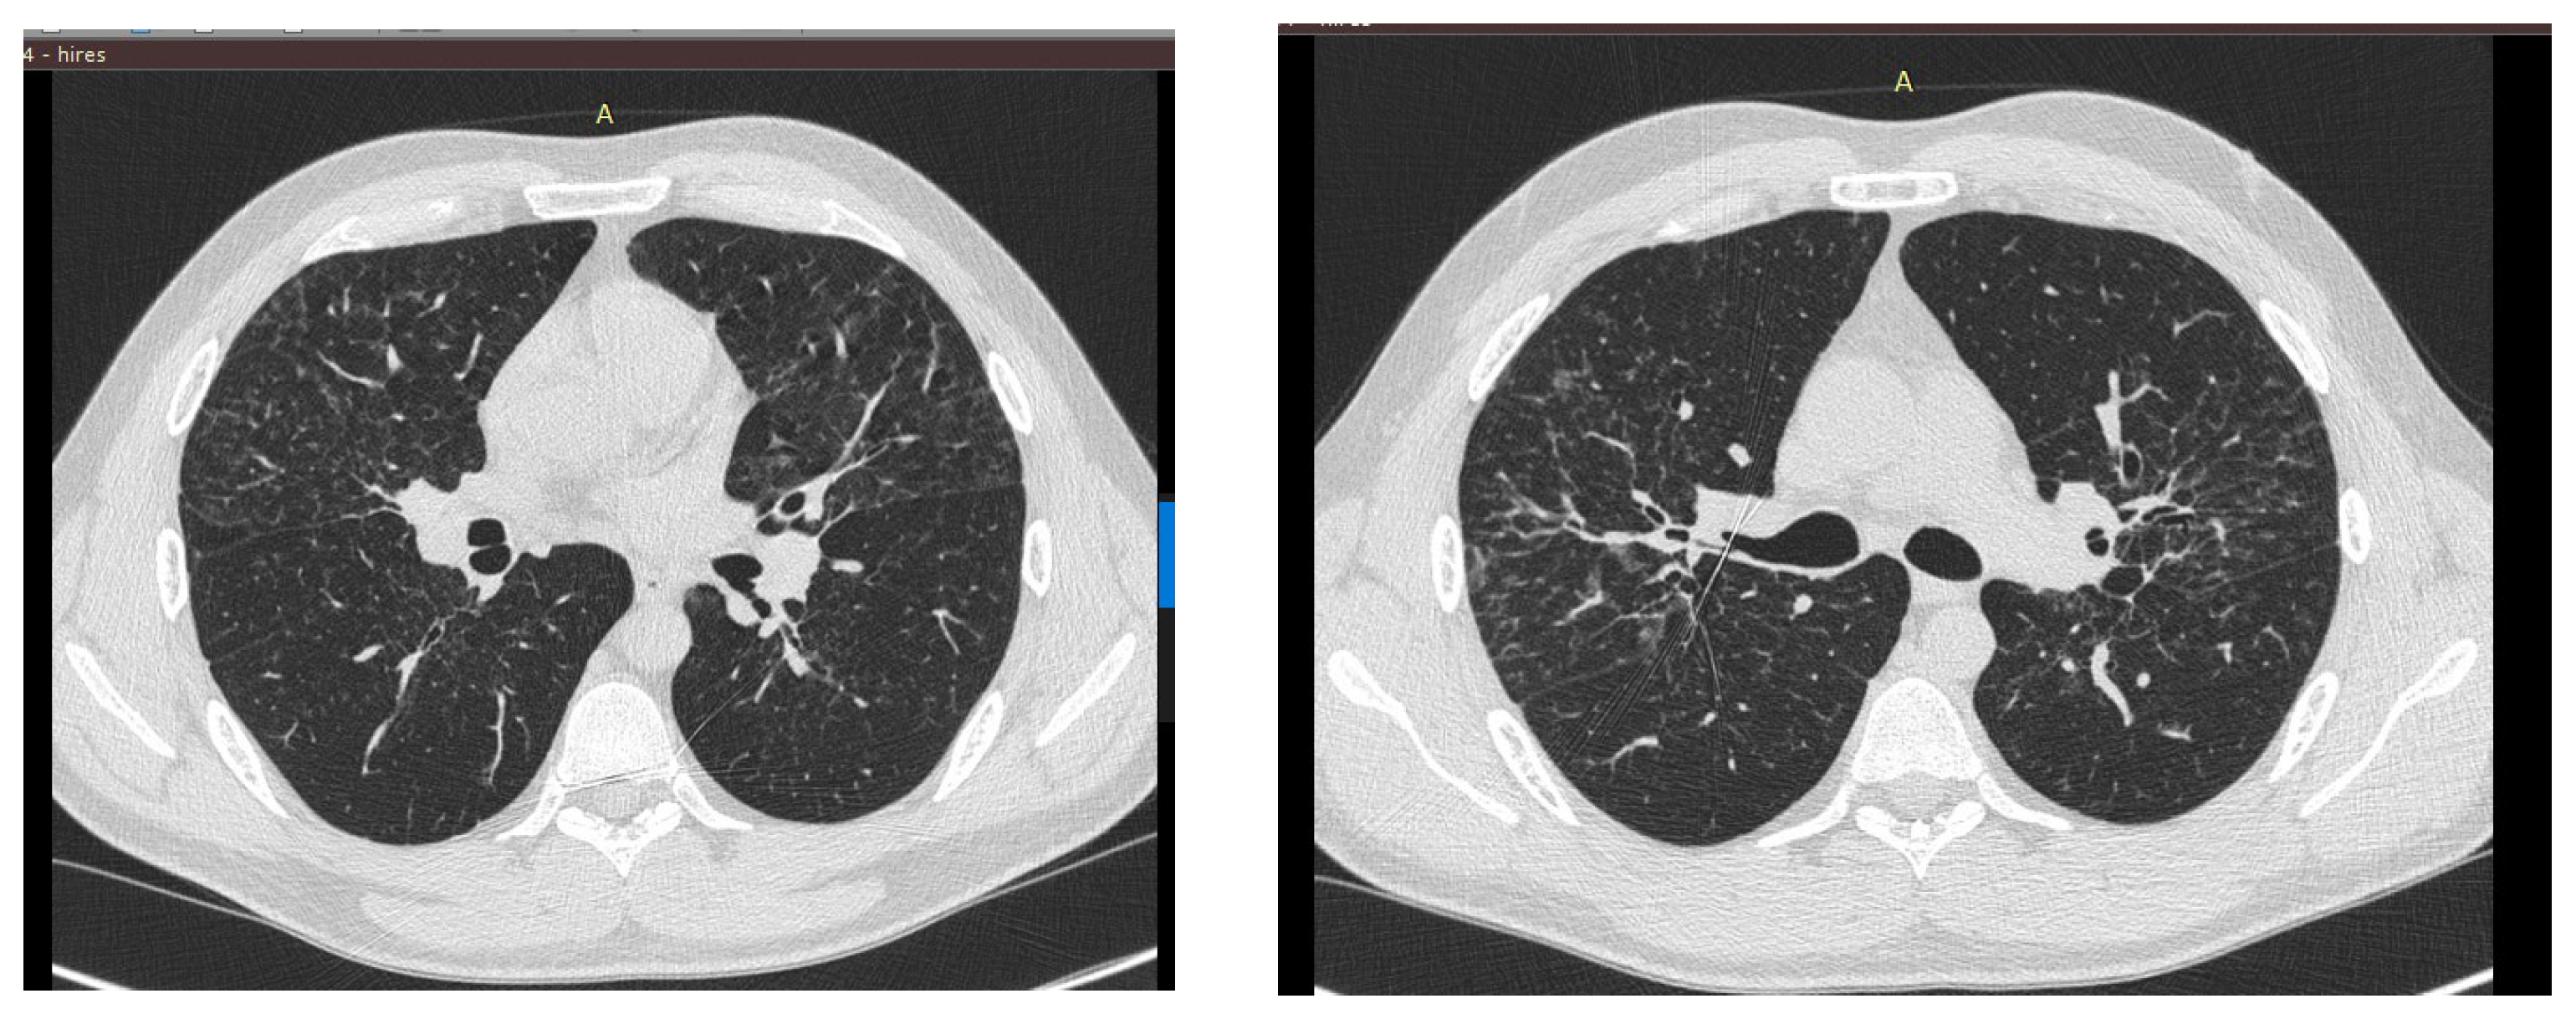

Body plethysmography was performed, which showed an increase in flow indices up to normal limits with positive dynamics of volumetric and capacitive indices: an increase in OEL (+19%) due to an increase in OOL (+6%) and LEF (+22%). CT of the chest also showed positive dynamics of the disease course. CT of the chest also showed positive dynamics (Figure 2).

Figure 2.

CT of the chest with positive dynamics.